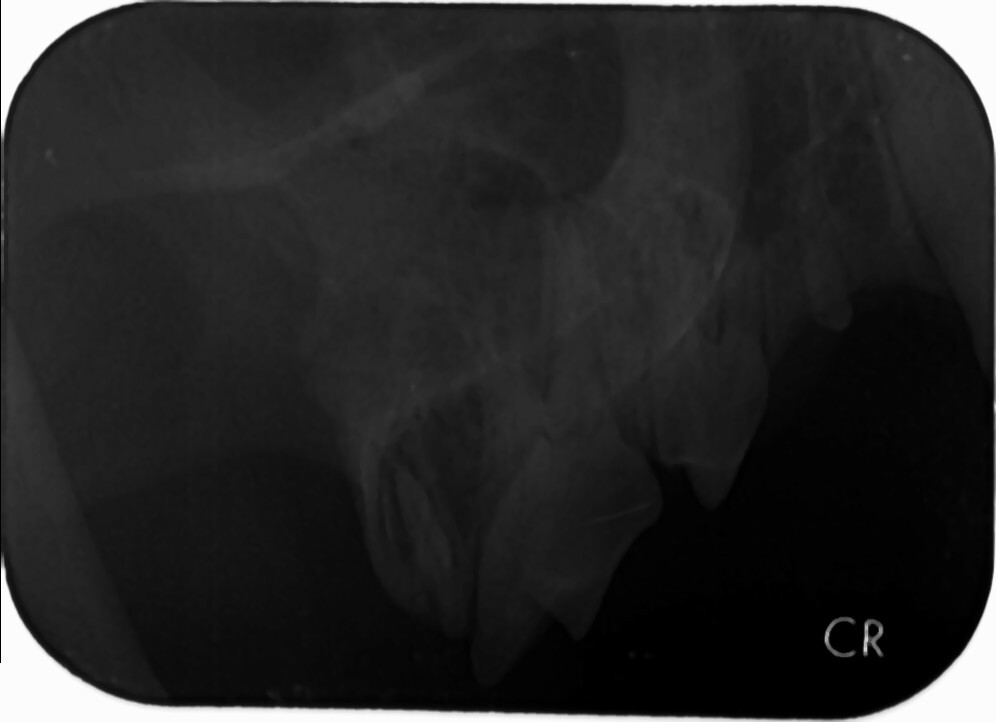

主題: 因長期鼻濃問題,至醫院拍攝口腔X光的藍寶 申請者姓名: 臺北市支持流浪貓絕育計劃協會 花色: 申請日期: 2017-08-31 17:14:35 申請者部落格: 申請者臉書網址: 所在縣市/合作醫院: 台北市/內湖維康動物醫院 治療費用: 6000元 需求人數: 14人 已結案 (2024-06-01 13:23:05) 報名人員: jerr(已付款)、李庭芝 x2(已付款)、ponton(已付款)、Andrea(已付款)、focustaco x2(已付款)、Naommi(已付款)、可樂 x2(已付款)、Eight(已付款)、Amber x2(已付款)、mason(已付款)、 候補人員: 動物病情說明: 因長期鼻濃問題而持續就診的藍寶

醫師檢查了藍寶的牙齒並再度安排至內湖維康動物醫院進行口腔x光的拍攝

確認了藍寶右上側P2齒根有瘺管,而齒根與鼻子相通

於是安排手術進行縫合

本筆維康費用即是藍寶針對口腔所做的X光拍攝